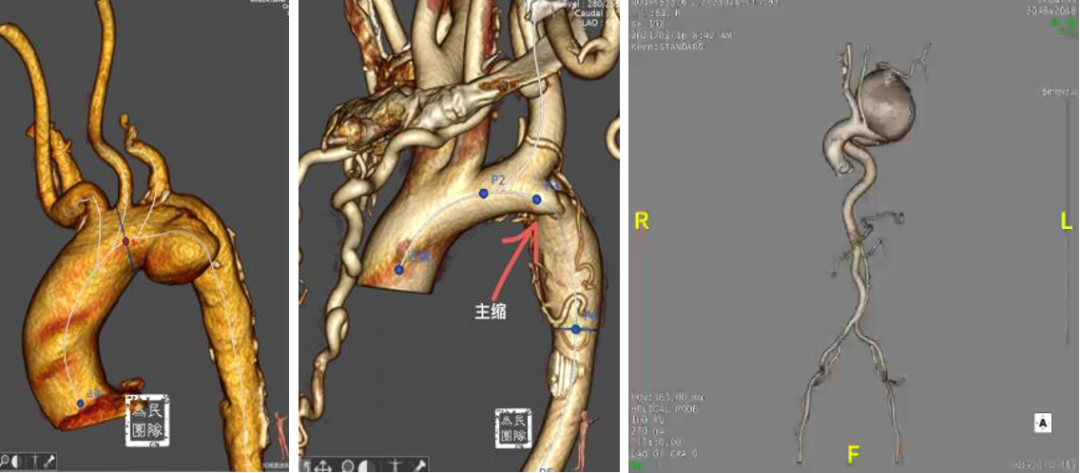

典型病例:一例TEVAR术后三个月发现内漏的患者,采用原位三开窗技术,依次开通左颈总动脉、头臂干、左锁骨下动脉。在有效脑保护下完成操作,术后七年随访效果理想。

另一例逆撕至头臂干的A型夹层患者,在ECMO辅助下行原位三开窗,术中虽出现心跳骤停,但通过ECMO模式转换成功救治,随访六七年CT显示良好。

复杂病例应用:巨大弓部动脉瘤(5.5cm)且左锁骨下动脉位于瘤腔内:在预开窗基础上加做左锁骨下动脉内嵌分支,配合3D打印模型辅助和束径技术,术后随访效果理想

A型夹层合并迷走左椎动脉:针对头臂干、左颈总和左锁骨下动脉进行预开窗,对非优势且纤细的迷走左椎动脉仅作小洞处理,术中对位良好